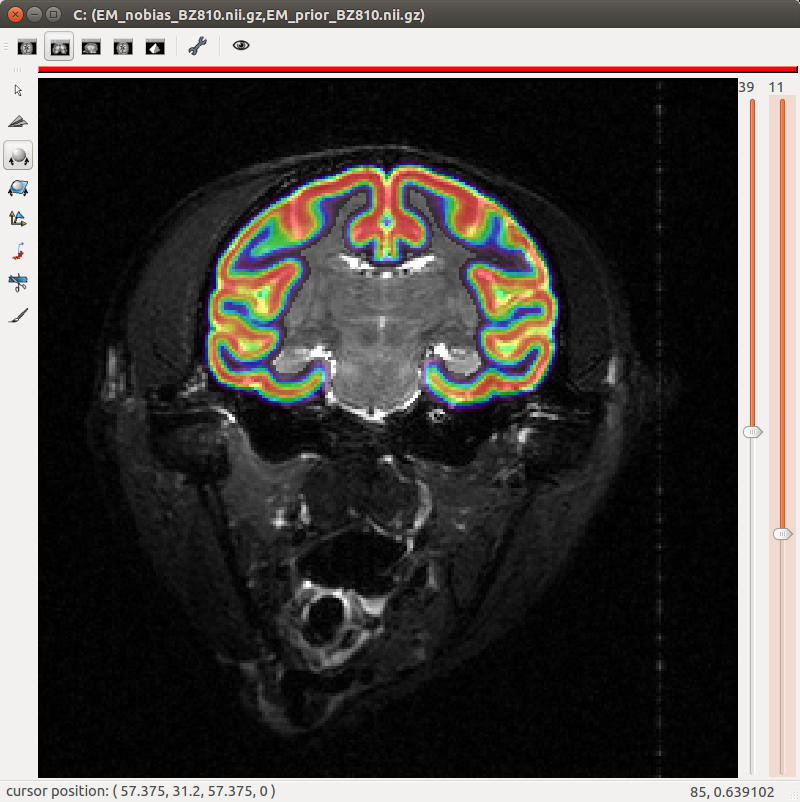

Primate segmentation toolbox

A segmentation toolbox dedicated to primate brain images is developed in MirCen, BioPicsel team. It is making use of some steps of the Morphologist pipeline, but is based on a probabilistic framework. It is designed to process macaque brains with T2 contrasts.